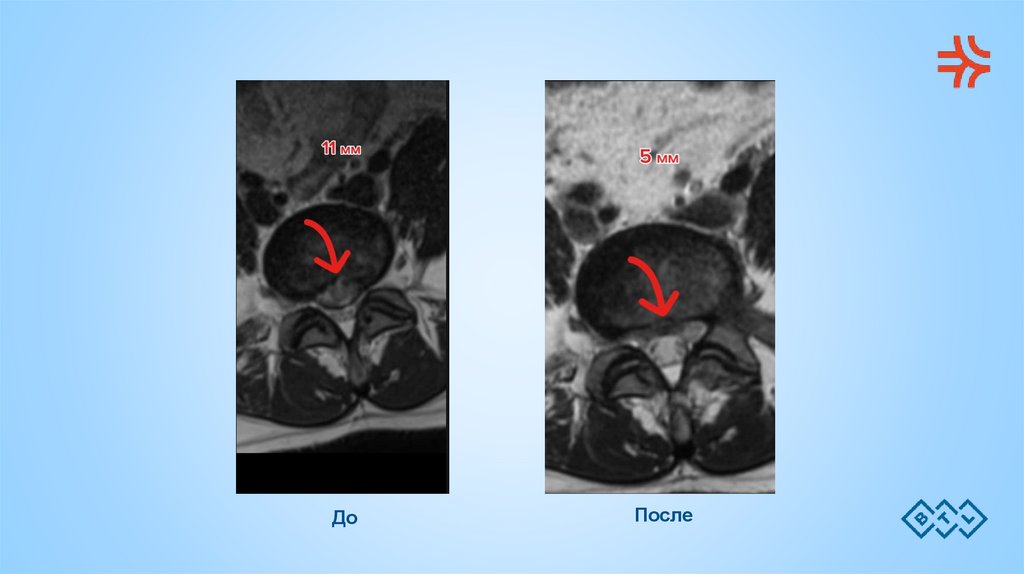

Пациентка Н, 43 г. Принята на HIL-терапию после

двух курсов амбулаторного лечения с применением

анальгетиков, НПВП, витаминотерапии,

электрофореза, массажа, магнитотерапии.

До

После